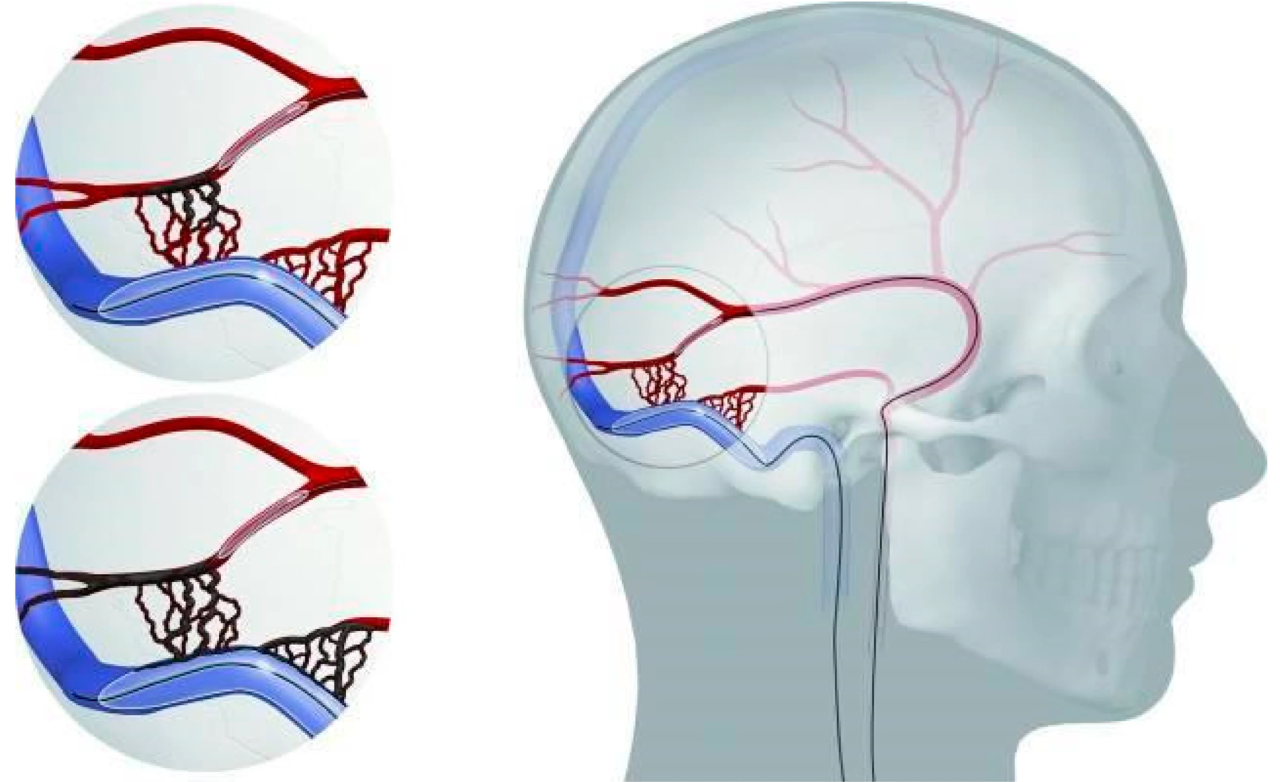

MMA embolization treats chronic subdural hematoma caused by repeated bleeding from fragile membranes around the brain.

By blocking the middle meningeal artery, the procedure reduces recurrence, supports healing, and may avoid repeat surgery.

Treats chronic subdural hematoma by blocking the middle meningeal artery, reducing recurrence and supporting faster, safer recovery.